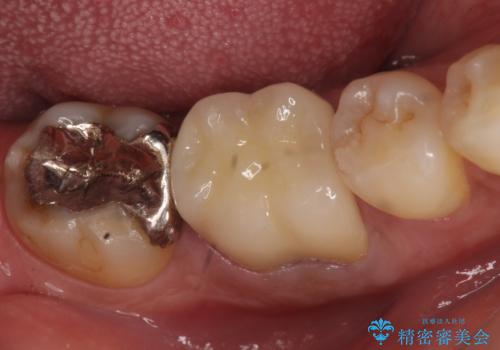

- 数年前から歯茎から膿が出る、治療してもよくならないので診て欲しいといらっしゃった方の症例です。

再根管治療を行い膿の出口の消失及び根尖病変の縮小を確認後、オールセラミッククラウンによる補綴を行いました。

今回用いたオールセラミッククラウンはジルコニアフレームという白い素材の上にセラミックを盛っているため、審美性が非常に高いのが特徴です。

また、ジルコニアは人工ダイヤモンドの材料にも使われているほど高い強度を持っており、そのためオールセラミッククラウンは審美性だけでなく、奥歯やブリッジの補綴も可能とするクラウンです。